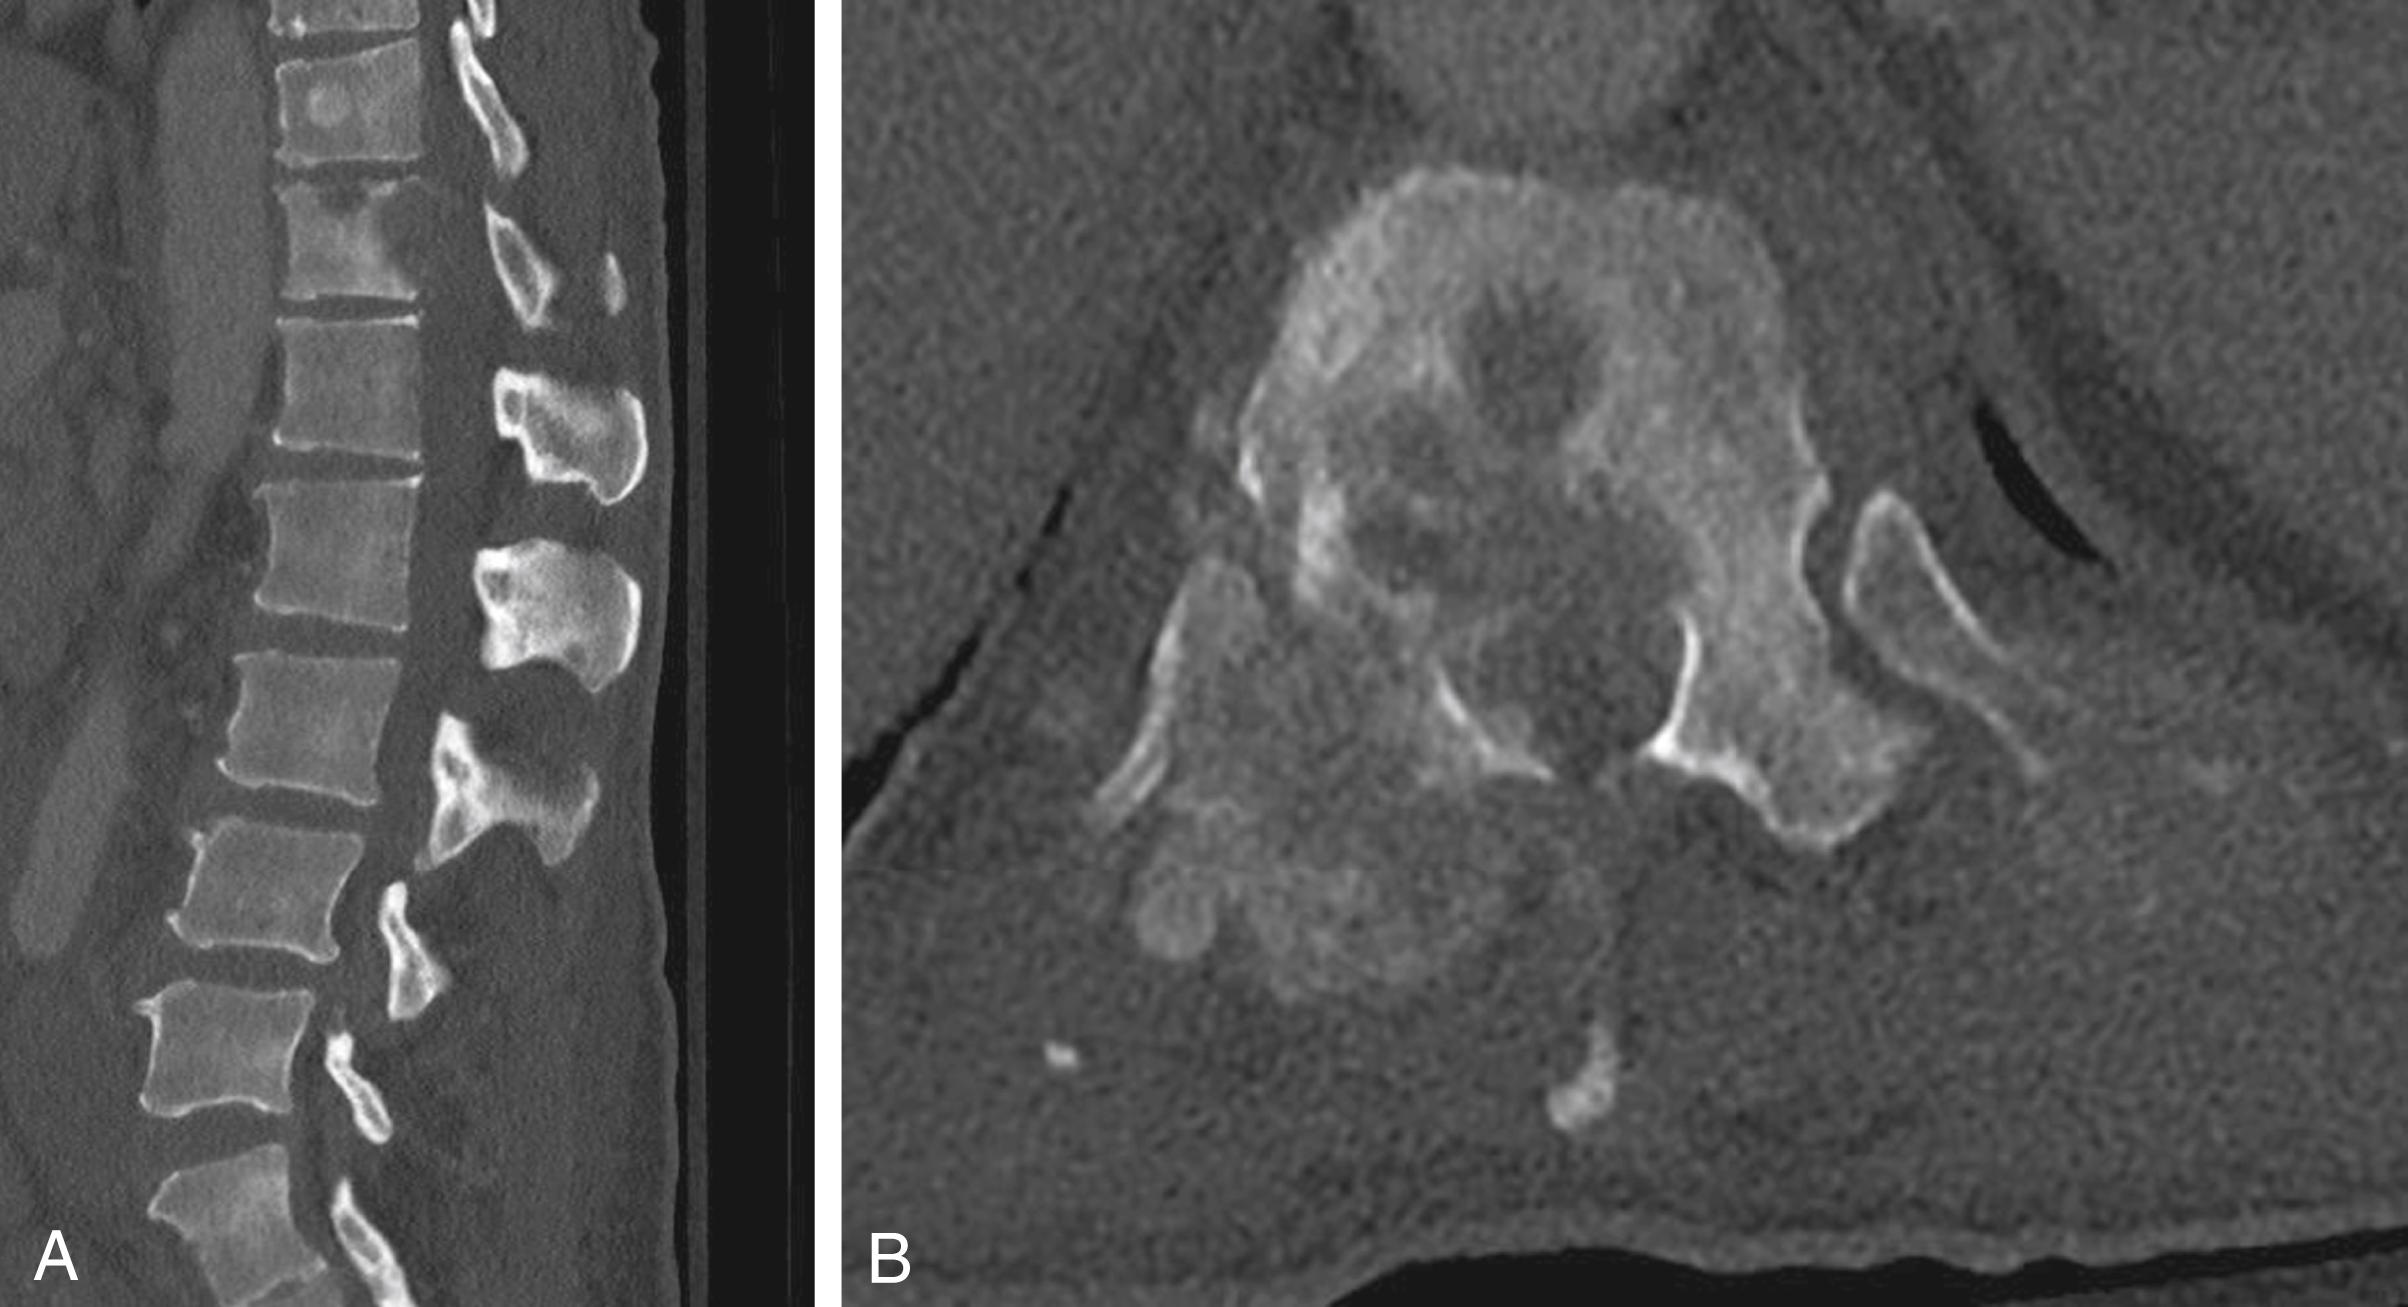

Fig. 42.1, A. Sagittal thoracolumbar CT without contrast demonstrates lytic lesions of the T12 vertebral body with normal alignment. There is no evidence of vertebral body collapse. There are diffuse intraosseous lesions throughout the spinal column (not pictured). B. Axial view demonstrates extraosseous extension of the T12 lesion into the ventral aspect of the spinal canal with involvement of the posterior elements (right worse than left).